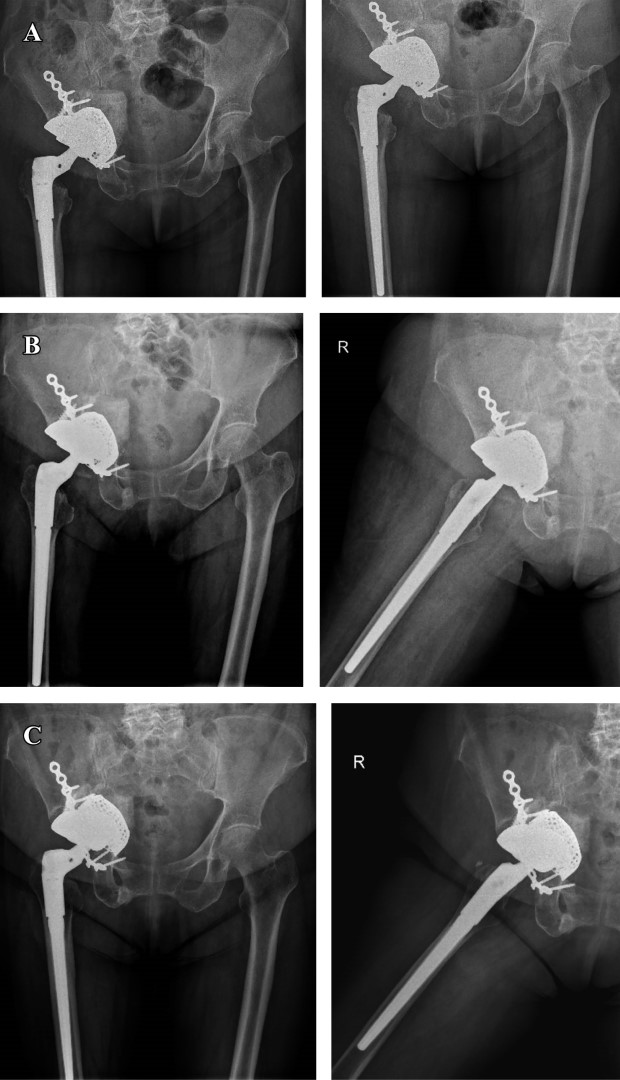

Se realiza seguimiento clínico y radiográfico a los 30, 60 días y al año, evidenciándose un Harris Hip Score final de 80 puntos y EVA de 0/10. No se evidencia migración medial de componente acetabular, además de adecuada osteointegración de los componentes protésicos (Figura 7).

Figura 7